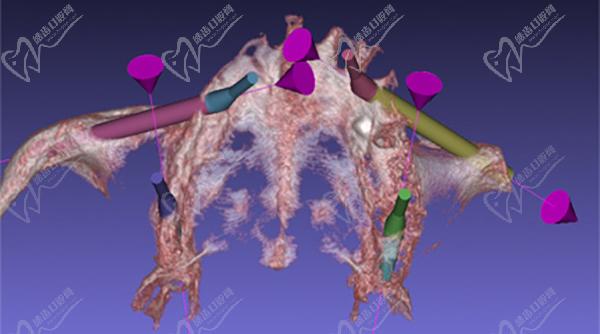

穿顴種植牙手術(shù)多久做完?

穿顴種植手術(shù)一般為上牙列穿顴種植、下牙列all-on-4種植,全口種植流程需要2.5小時(shí)完成,實(shí)現(xiàn)一日得穿顴種植技術(shù)。術(shù)前進(jìn)行全口CT掃描、3D頭骨模擬重建等,精細(xì)確認(rèn)牙友骨量不足的程度、上頜竇底骨質(zhì)薄的數(shù)據(jù),確保手術(shù)更安心。

在做穿顴種植手術(shù)的時(shí)候,因?yàn)橛袃深w植體斜插入顴骨貫穿面部神經(jīng)和血管區(qū),所以,需要在術(shù)前進(jìn)行詳細(xì)的CBCT頜面檢查,提取上頜竇等影響數(shù)據(jù)來確定非常精密的植入方案,來避免損傷神經(jīng)。大家做穿顴種植手術(shù)的時(shí)候切記要選擇正規(guī)醫(yī)院。

醫(yī)生要詳細(xì)了解術(shù)區(qū)的臨近動(dòng)脈、靜脈、神經(jīng),且植體長(zhǎng)度是常規(guī)植體的3-5倍長(zhǎng),起端極小的角度偏差都會(huì)導(dǎo)致末端的巨大偏離,造成手術(shù)失敗或損傷神經(jīng)的風(fēng)險(xiǎn),手術(shù)精細(xì)度非常高。